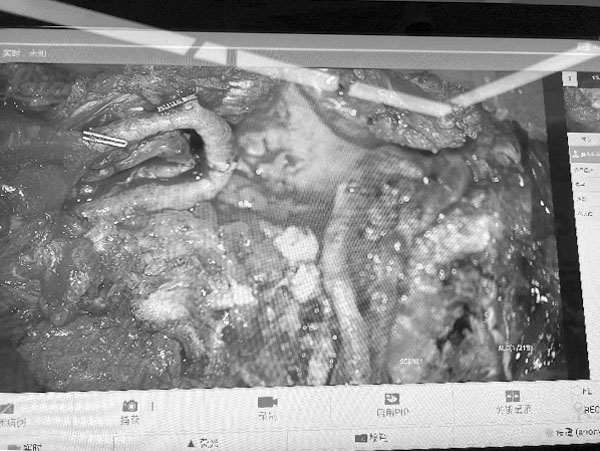

回天立、王新乐副主任医师显微镜下精细操作

电子显微镜放大10倍后小血管的吻合

游离腹壁下动脉穿支皮瓣自体组织重建术(Deep Inferior Epigastric Perforator Flap,DIEP)是一种利用患者自身腹部皮肤、脂肪及血管进行乳房重建的显微外科手术。该技术通过显微外科手段将腹壁下动脉穿支血管与胸壁血管吻合,实现组织存活,具有创伤小、保留腹直肌功能的特点。其技术特点包括:在显微镜下完成精细血管吻合,确保移植皮瓣的血供;供区损伤小,仅切取腹部脂肪及皮肤,完整保留腹直肌结构,术后恢复更快;重建乳房形态自然持久,触感与外形接近真实乳房,避免了假体相关的包膜挛缩等问题;同时实现腹部整形与乳房重建的双重效果。

DIEP手术代表着自体组织乳房重建的技术高点,其核心在于显微镜下完成细小血管吻合,使离体皮瓣恢复供血并塑形为对称的乳房形态。这一过程需以精准稳定的显微外科技术为支撑,与整形外科理念实现深度融合,二者的协同,是操作成败的关键。